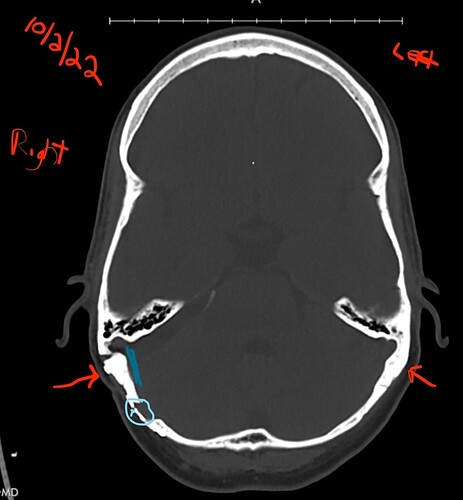

I really do not know if this is an artifact of the imaging but the area (Cyan circle & tiny arrow) point to an area which appears to be thinned compared to the contralateral side. Based on some research, MVD can also cause post-surgery CSF leaks. So it won’t hurt to bring it to their attention since they are going to be drilling the bone.

Funny how it’s too thick in some areas and too thin in other areas.